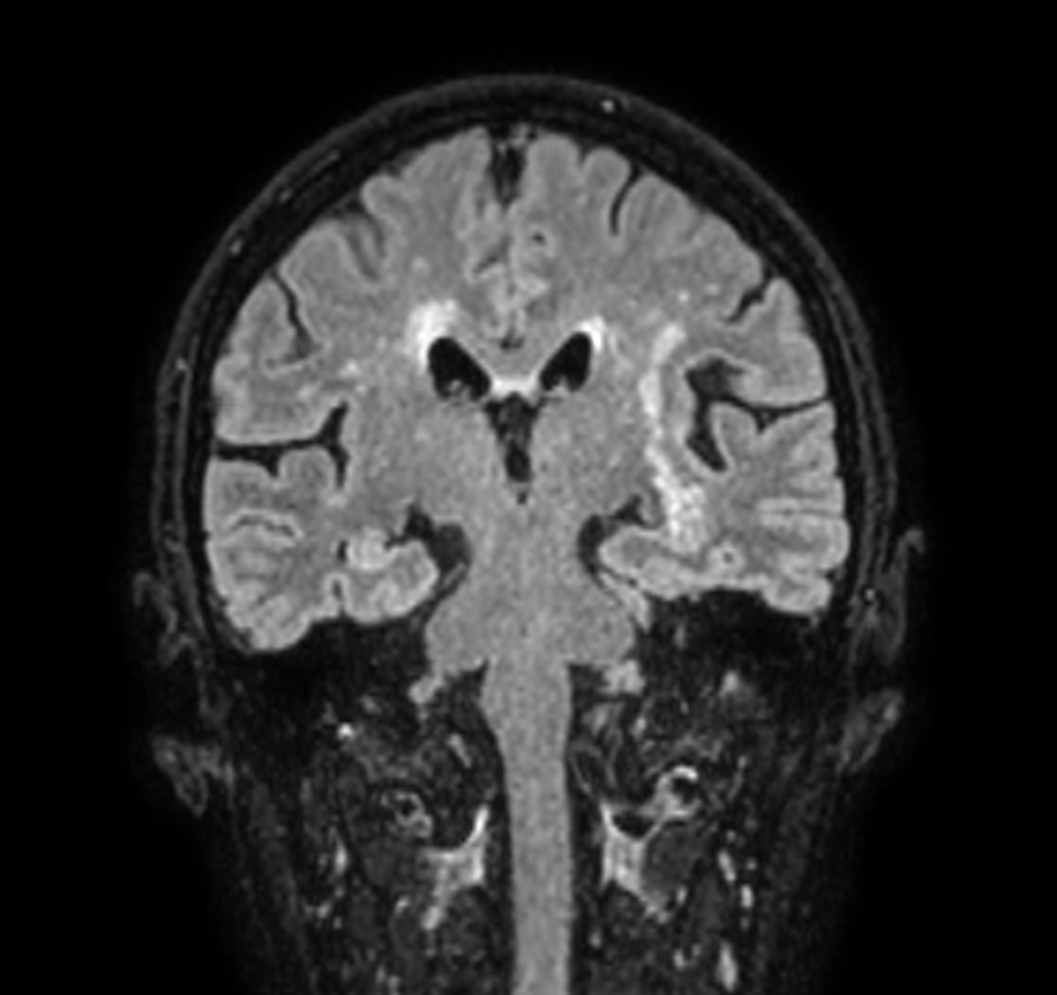

3D VIEW - T2w FLAIR (coronal reformat)